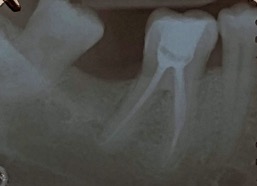

Un trattamento endodontico consiste nel salvare un dente compromesso da carie, traumi o fratture rimuovendone polpa e nervi infetti/infiammati responsabili di dolore, ascessi, cisti e granulomi.

Un adeguata endondonzia serve per salvare quei denti che altrimenti sarebbero destinati ad essere estratti. Quando un dente viene devitalizzato viene privato della sua irrorazione sanguigna e del nutrimento, rendendo la sua struttura più “vetrosa” quindi più fragile e soggetta a fratture. Per questo motivo è consigliabile nella maggior parte dei casi capsulare i denti una volta che hanno perso la loro vitalità.

L’endodonzia è una branca complessa dell’odontoiatria, richiede precisione, una lunga curva di apprendimento oltre che all’imprescindibile capacità di utilizzare degli ingrandimenti adeguati. Il Dott. Galimberti Gabriele, esperto in endodonzia, è arrivato a trattare più di 1200 denti all’anno.